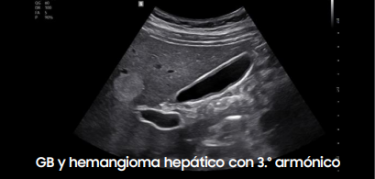

Galería de imágenes